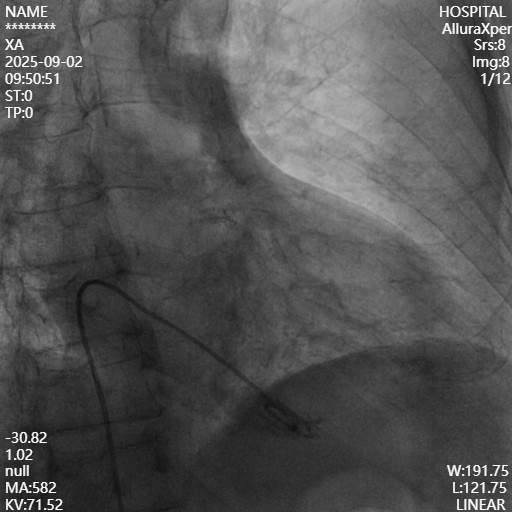

造影自肘静脉至腋静脉段逐渐变窄变细,直至消失,判定左侧无传统起搏器入路路径,改右侧植入,多次穿刺,再次失败,行静脉造影。

造影发现自肘静脉行至腋静脉段逐渐变窄直至消失,右侧同样不具备入路条件。